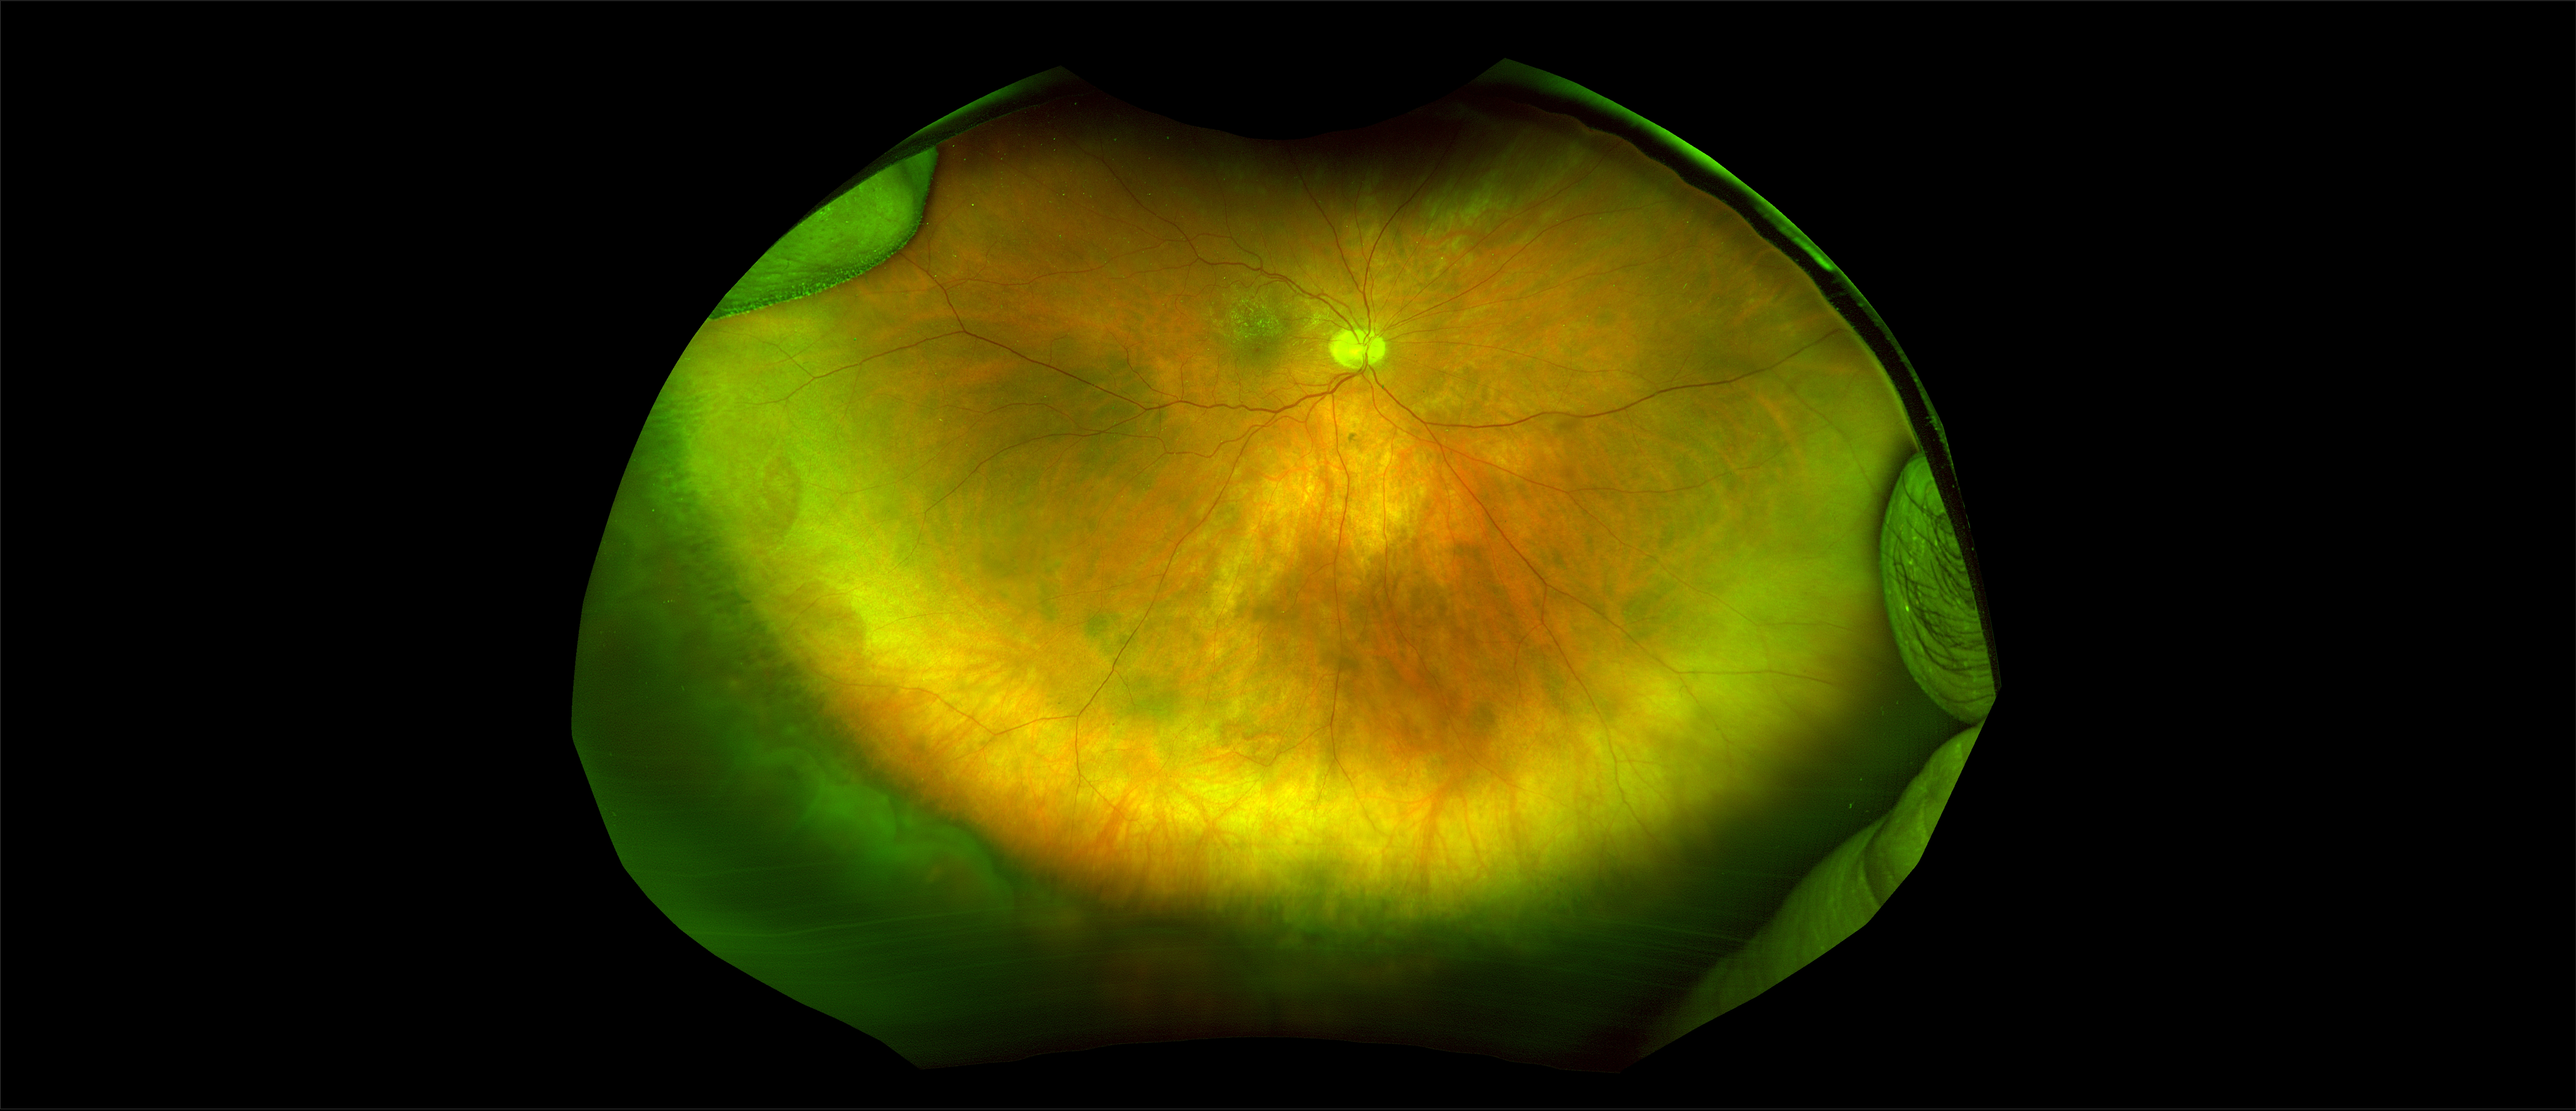

California - Large Pars Plana Cysts - Steered, RG

Pars plana cysts are a common peripheral retinal pathology that do not raise much clinical concern. They do not affect the central vision and observation alone is typically recommended. Pars plana cysts are something to be considered when peripheral retinal elevation is noted on routine exam.